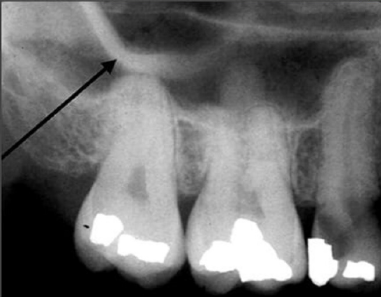

43. What is the anatomical structure indicated by arrow in this radiograph?

Maxillary Sinus The borders of the maxillary sinus appear on periapical radiographs as a thin, delicate, tenuous radiopaque line. In adults the sinuses usually extend from the distal aspect of the canine to the posterior wall of the maxilla above the tuberosity. In older adults the sinus may extend farther into the alveolar process, and in the posterior region of the maxilla its floor may appear considerably below the level of the floor of the nasal cavity. Anteriorly each sinus is restricted by the canine fossa and is usually seen to sweep superiorly, crossing the level of the floor of the nasal cavity in the premolar or canine region. Consequently, on periapical radiographs of